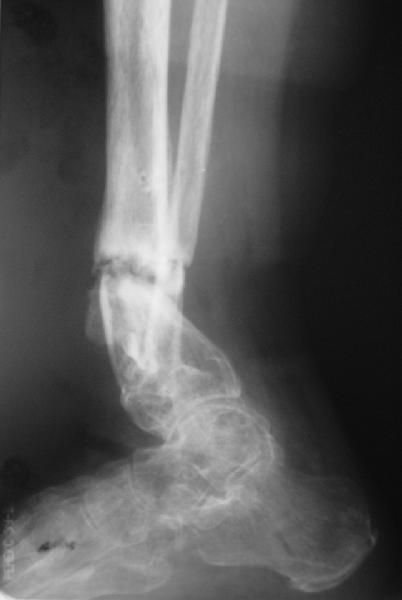

Глубокоуважаемые коллеги,Поступила женщина 72 лет. Полтора года назад - укушенная рана, перелом голени. Лечили аппаратом, не срослось. Долго не заживала рана.

Но вроде уже с полгода мягкие ткани закрыты. Спереди подпаянные рубцы. Есть приличная подвижность на уровне несращения. Картинки в приложении. Что предложите? Спсибо заранее.

Why the need for the Ilizarov if the nonunion is mobile? I would correct the deformity acutely with a fibular osteotomy if necessary to correct the

alignment and proceed with reamed IM nailing if there are no signs or history of infection. Minimum of 2 and preferably 3 distal locks, and put in a big enough nail to get a good isthmal fit. I reported a series of similar cases with an excellent success rate.

There are two fractures of the fibula. One the obvious one, and the second just above the syndesmosis. I would try to have a wire transfixing the lower tibial and fibular fragments.